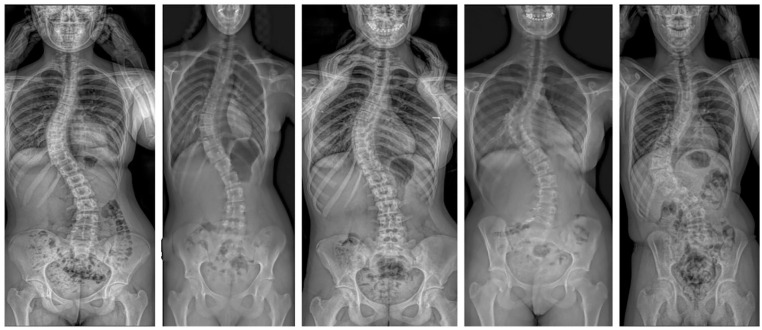

Abstract Image